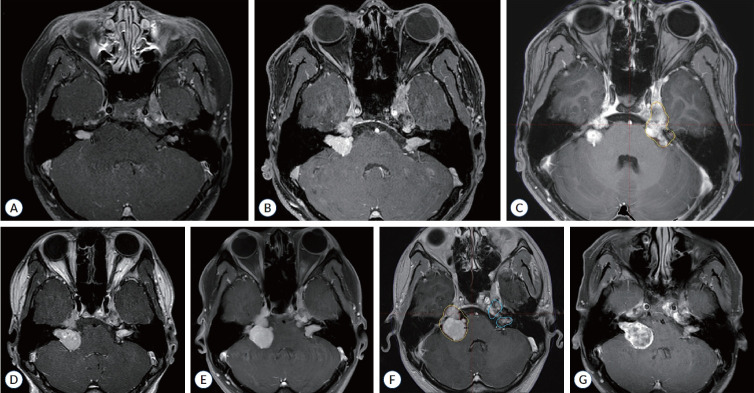

Abstract Image